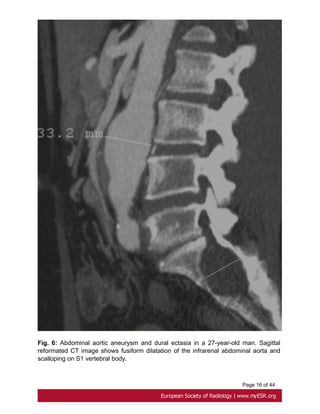

24mm in the abdomen[7]. Fig. 6 on page 15

Fig. 6: Abdominal aortic aneurysm and dural ectasia in a 27-year-old man. Sagittal

reformated CT image shows fusiform dilatation of the infrarenal abdominal aorta and

scalloping on S1 vertebral body.

Page 16 of44 Fig. 6: Abdominal aortic aneurysm and dural ectasia in a 27-year-old man. Sagittal reformated CT image shows fusiform dilatation of the infrarenal abdominal aorta and scalloping on S1 vertebral body.